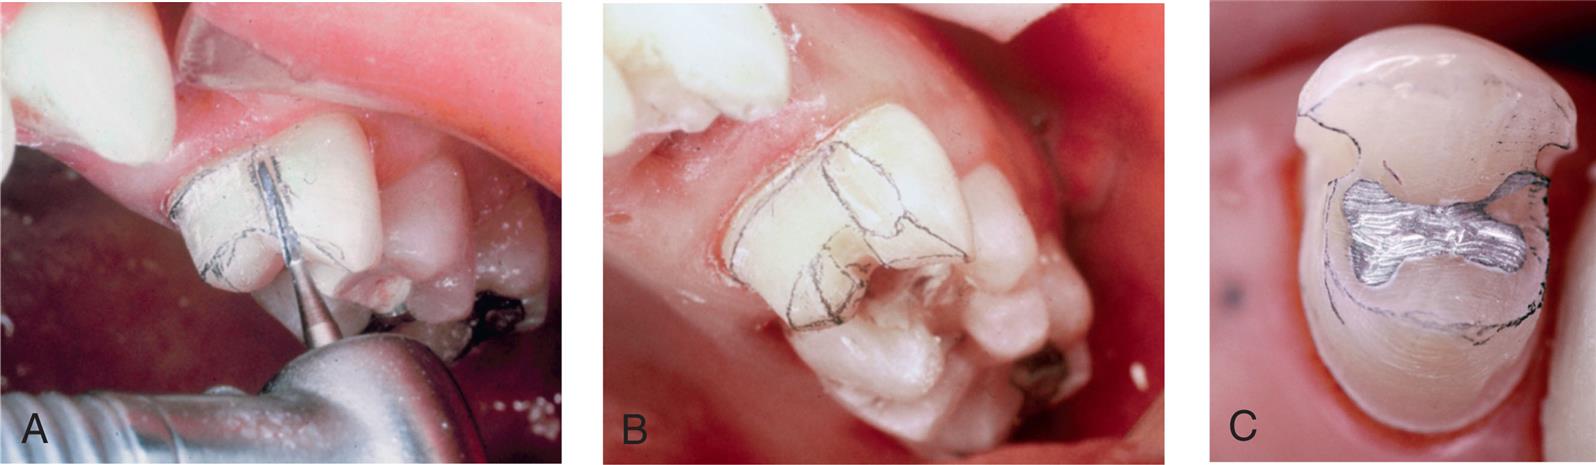

The step-by-step preparation of a three-quarter crown is illustrated on a maxillary premolar (Fig. 11.4). Except for a narrow bevel or chamfer margin placed along the bucco-occlusal line angle, the buccal surface of the abutment remains intact. The other surfaces (including the occlusal surface) are prepared to accommodate a casting in the same manner as a complete crown preparation (see Chapter 8), differing only in the need for proximal axial grooves to develop resistance form.

The proximal grooves are best prepared with a tapered tungsten carbide bur.

Depending on available access, it may be feasible to complete the flaring with the same rotary instrument that was used to place the groove (Fig. 11.13). However, removing the last “lip” of unsupported tooth structure with a chisel is often a better option because this minimizes the risk of damage to the adjacent tooth.

Although largely surpassed in popularity by adhesively bonded ceramic restorations—at least for restoration of single teeth—a few clinical examples of other types of cast partial veneer crowns are illustrated to help understand the geometry of their preparation designs and since they still may be encountered clinically. Fig. 11.18 shows the design of a seven-eighths crown on a maxillary molar and a clinical example. A modified three-quarter crown used as a retainer for a three-unit FPD is illustrated in Fig. 11.19.